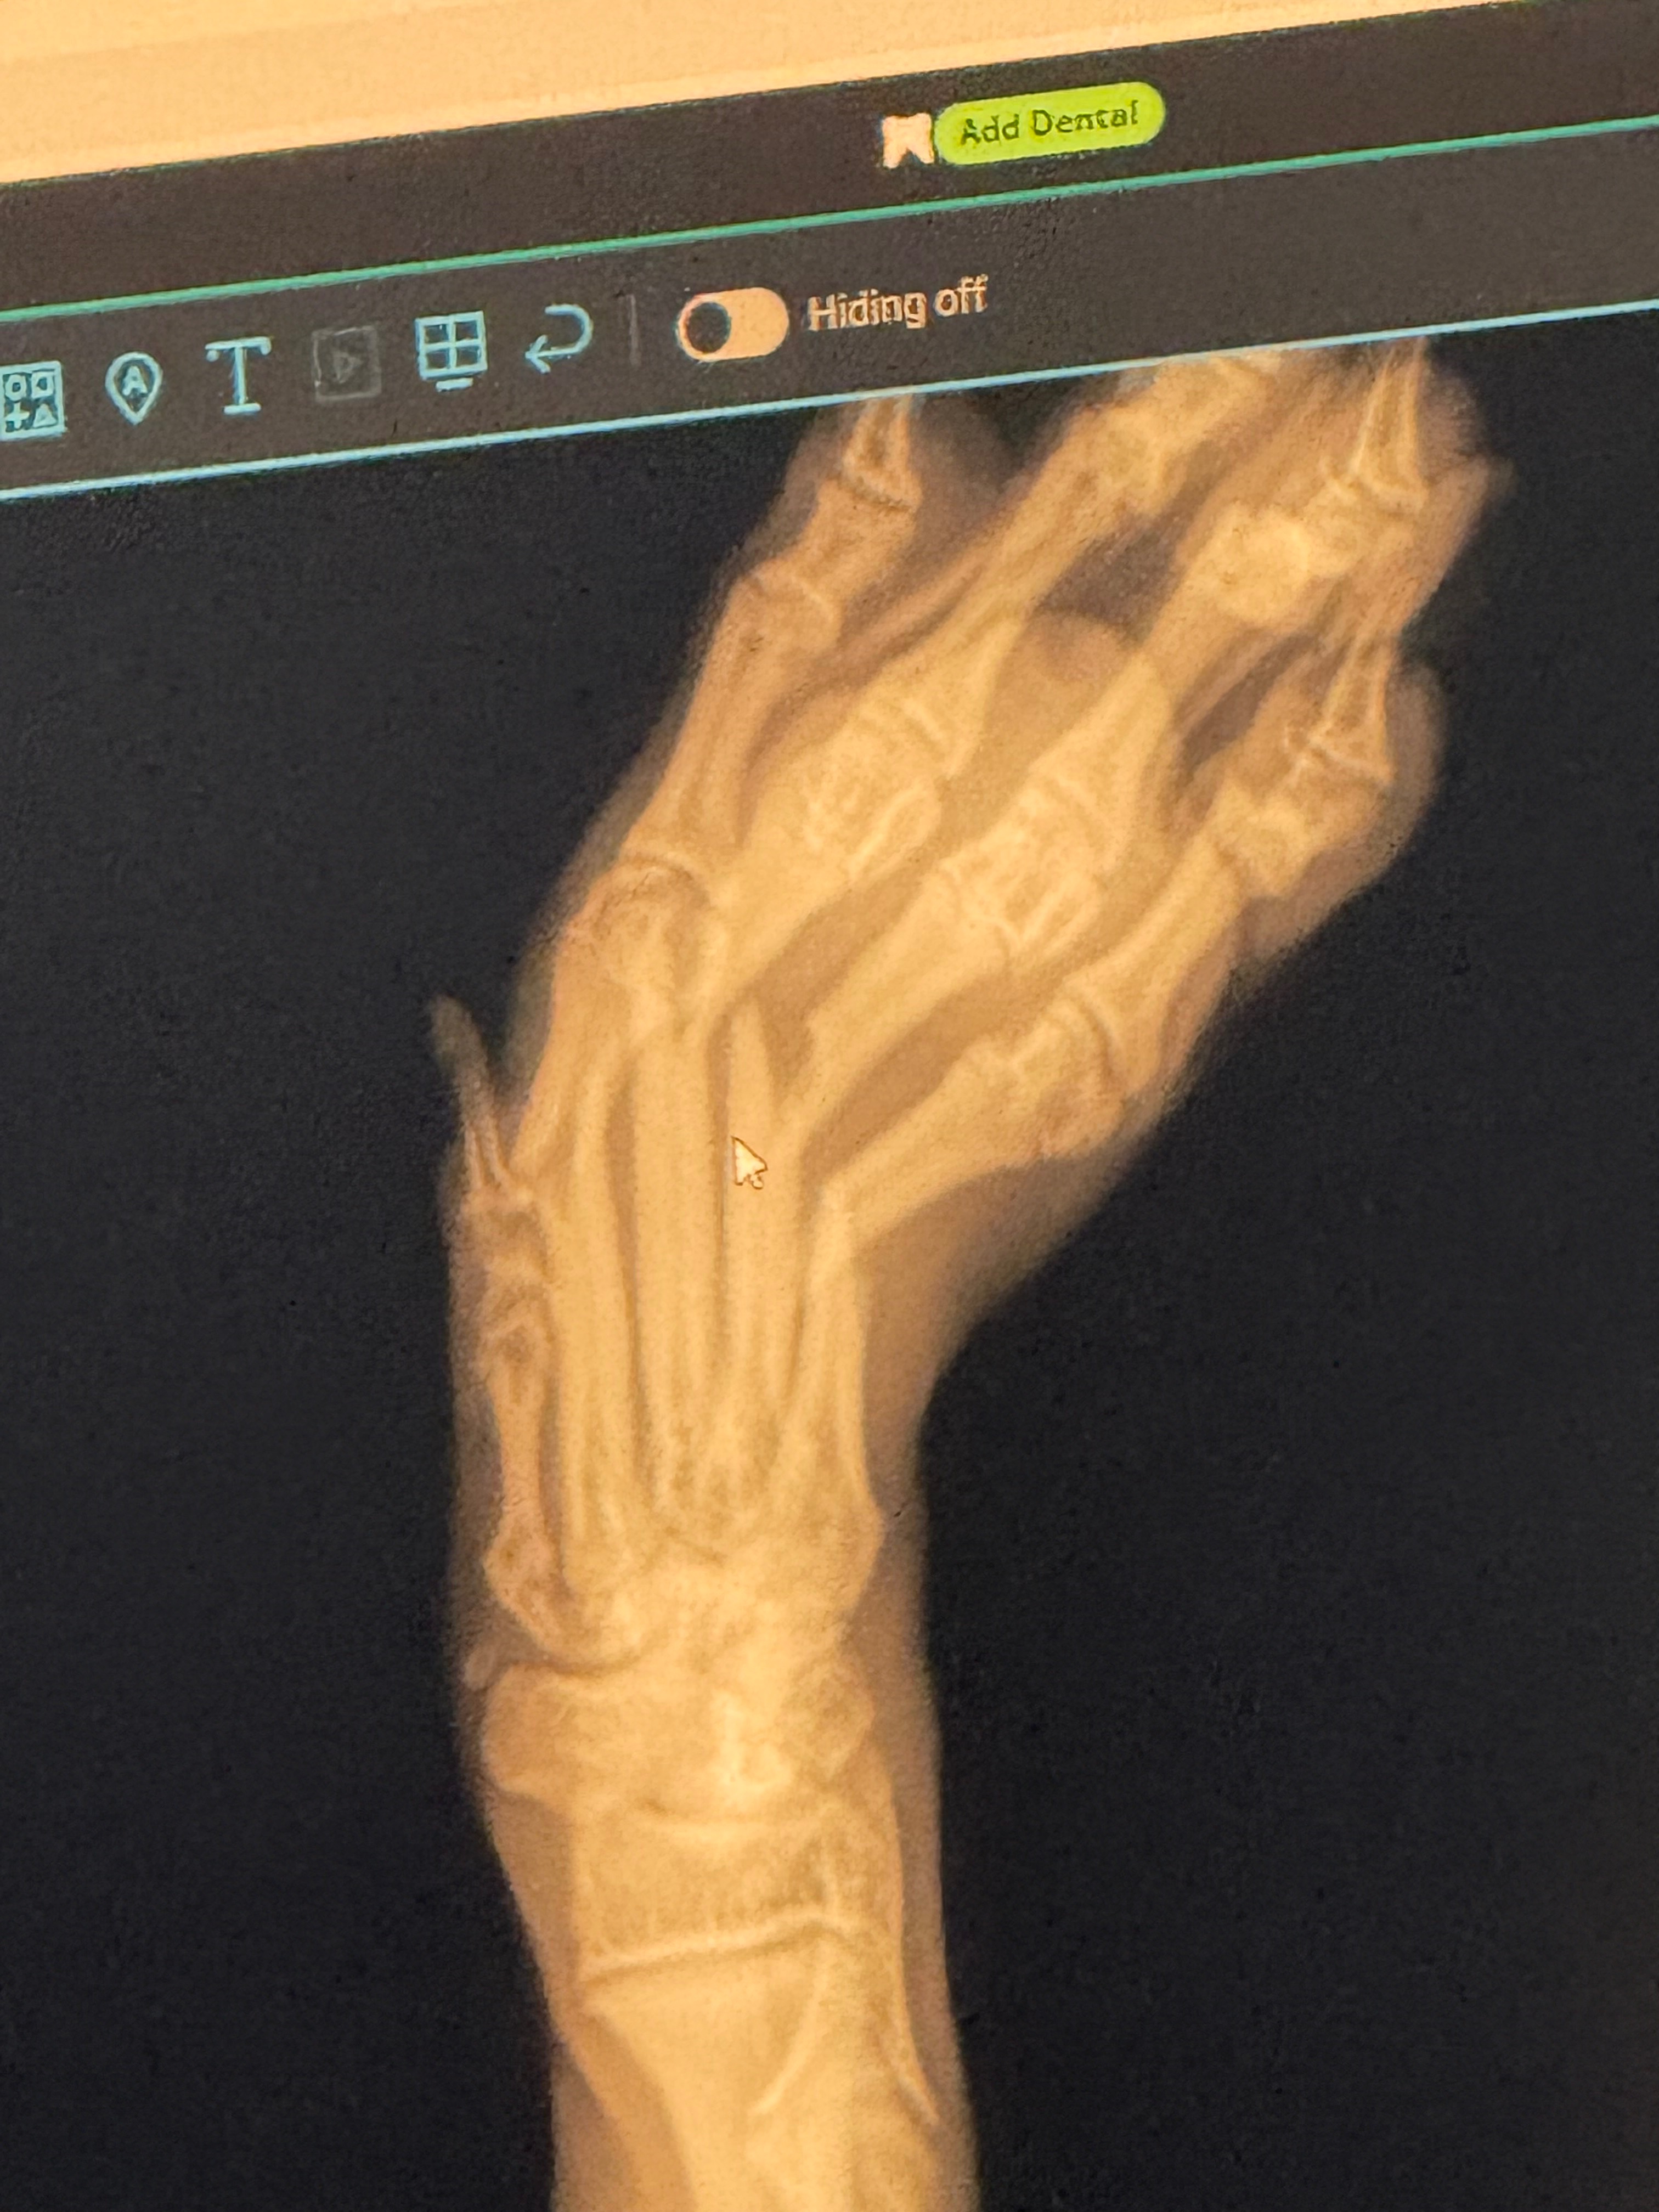

While I was carrying her, she unexpectedly jumped from my arms and landed the wrong way. We rushed her to the emergency vet, terrified something was wrong. After X-rays, we received devastating news — Lilith broke four toes on her front paw.

The fractures are severe. The vet told us she needs to see an orthopedic specialist immediately and will likely require surgery to properly repair the bones. Without surgical intervention, her paw may heal incorrectly, leaving her with long-term pain, mobility issues, or permanent damage.